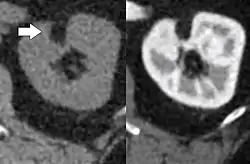

| Angiomyolipoma in both kidneys (arrows) as seen on CT scan. The tumors are hypodense (dark) due to fat content. | |

CT scan of a renal angiomyolipoma. It involves the renal cortex, and has an attenuation of less than 20 HU on the Hounsfield scale, which are typical characteristics.[8]